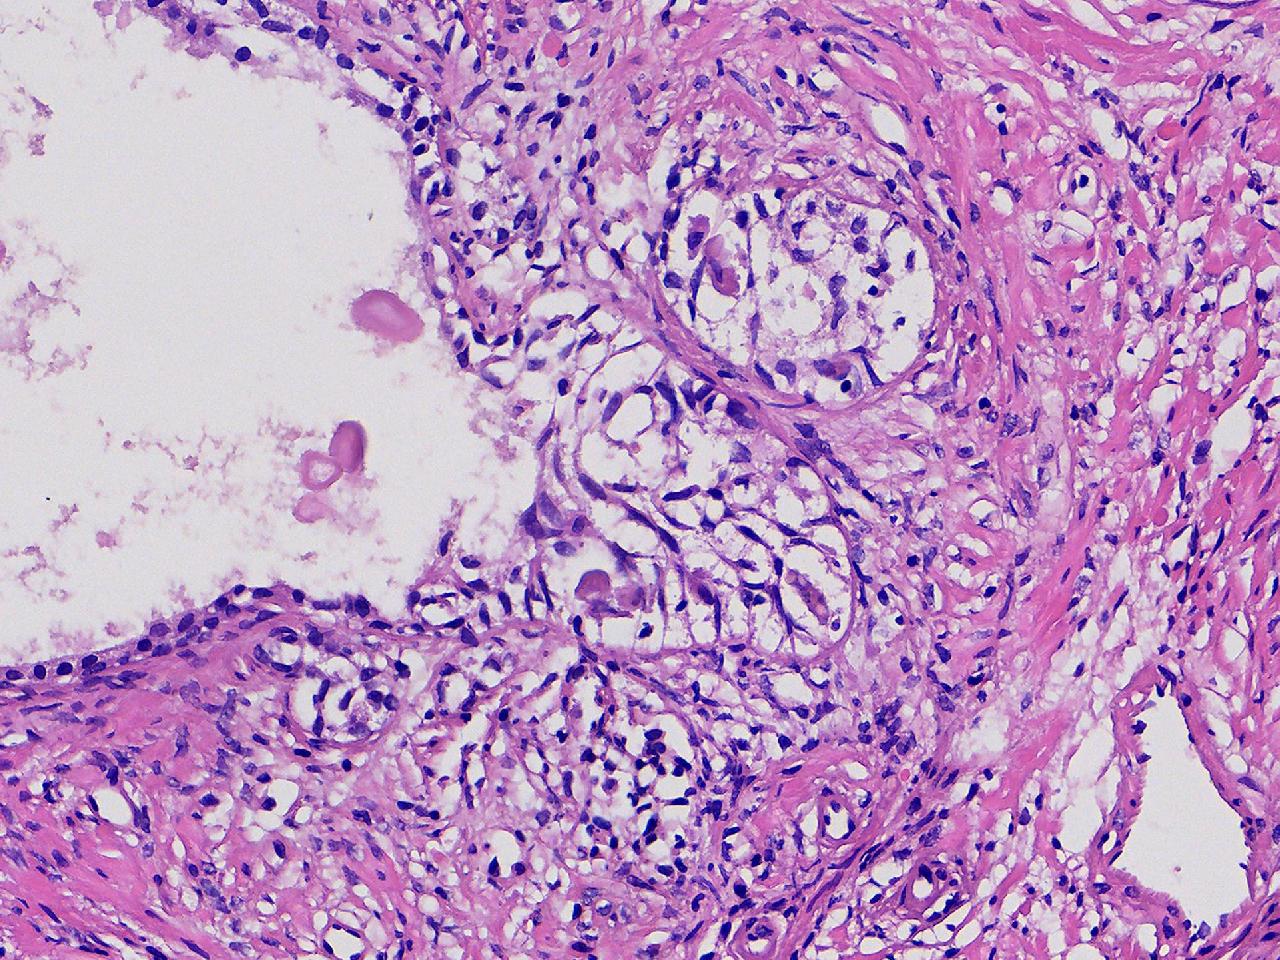

良性前列腺增生吧?

性别

男

年龄

65岁

临床诊断

前列腺电切组织

一般病史

进行性排尿困难半年余。

标本名称

前列腺

大体所见

图4

、良性前列腺增生

BPH.